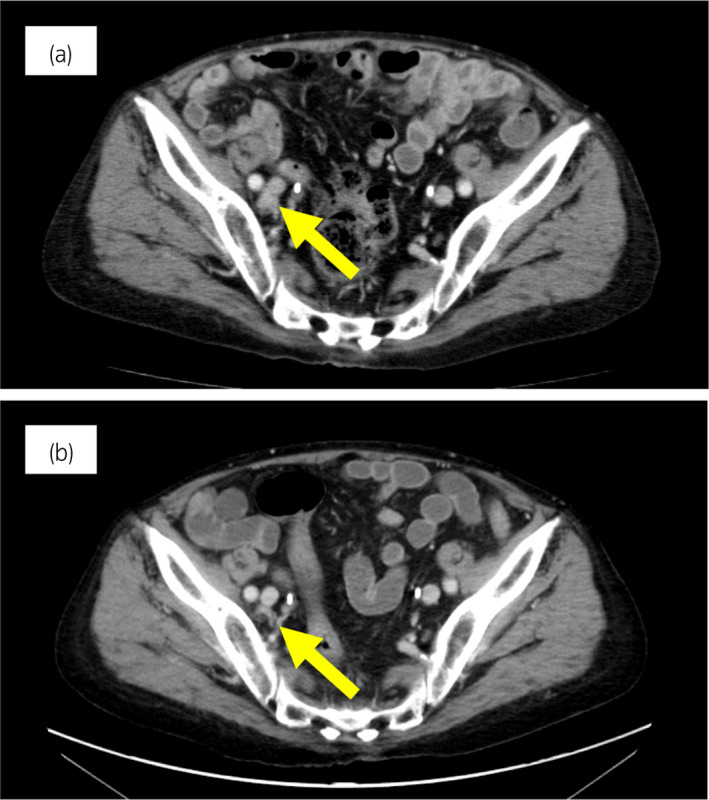

70 歲男性被診斷為轉移性 PC,cT3bN1M1b,Gleason 評分(GS)為 4 + 5 = 9,前列腺特異性抗原(PSA)水平為 40.8ng/ml,3 年前伴有胸椎轉移。 對前列腺進行聯(lián)合雄激素阻斷 (CAB) 治療和質子放射治療 (78.0Gy/39fr)。 PSA 水平降至 <0.01ng/ml,CAB 在 2.5 年后停止。 停止 CAB 五個月后,他出現(xiàn)背痛,PSA <0.01 ng/ml。 計算機斷層掃描 (CT) 掃描檢測到多處肝、骨和淋巴結轉移,神經元特異性烯醇化酶 (NSE) 水平高達 171ng/ml(圖 1a)。 骨轉移活檢顯示神經內分泌前列腺癌 (NEPC) 的診斷(圖 2),患者被轉診至佳學基因合作醫(yī)院。 內分泌腫瘤正確治療醫(yī)生用順鉑、依托泊苷和亮丙瑞林治療。 第三個療程后,轉移部位明顯縮小(圖 1b)。 順鉑和依托泊苷治療 1 年,但患者因神經病變要求停藥。 他開始服用恩雜魯胺。 治療 3 個月后,患者出現(xiàn)背痛和左鎖骨下淋巴結腫大(圖 3a)。 肝轉移保持不變,順鉑治療后縮小。 通過腫瘤正確用藥850基因檢測證實了 BRCA2 突變。根據(jù)基因檢測結果,主治腫瘤科醫(yī)生給予了奧拉帕尼。 三個月后,背痛好轉,淋巴結轉移縮小,確定為部分緩解(PR)(圖3b)。 肝轉移灶保持不變。

圖 3:案例 1. 開始使用奧拉帕尼之前和之后 3個月的鎖骨下淋巴結轉移的 CT 圖像。 (a) 治療前和 (b) 奧拉帕尼治療后 3 個月。 黃色箭頭顯示轉移淋巴結。